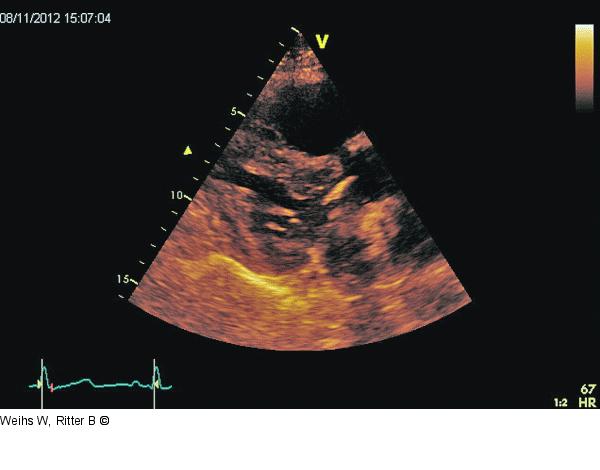

Abbildung 1: Parasternaler Längsschnitt Parasternaler Längsschnitt: Kleiner hyperkontraktiler linker Ventrikel. Leichte Klappensklerose. Dilatation und Hypokontraktilität des rechten Ventrikels. |

Parasternaler Längsschnitt: Kleiner hyperkontraktiler linker Ventrikel. Leichte Klappensklerose. Dilatation und Hypokontraktilität des rechten Ventrikels. |